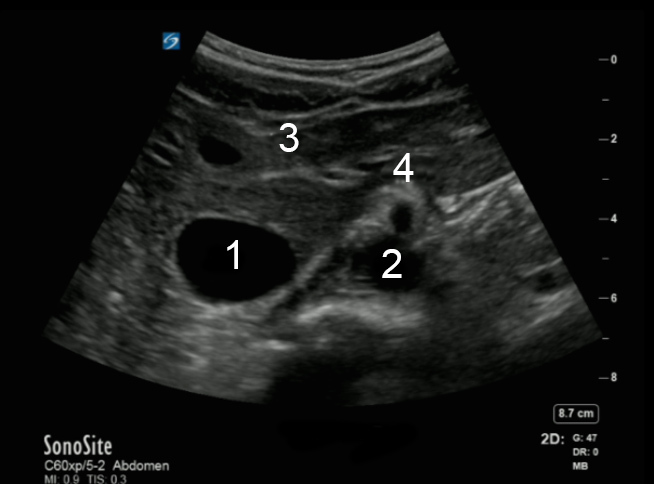

Bild: Aorta, Arteria mesenterica superior (AMS), transversal

1. Vena cava inferior (VCI)

2. Aorta (Ao)

3. Leber

4. Arteria mesenterica superior (AMS)